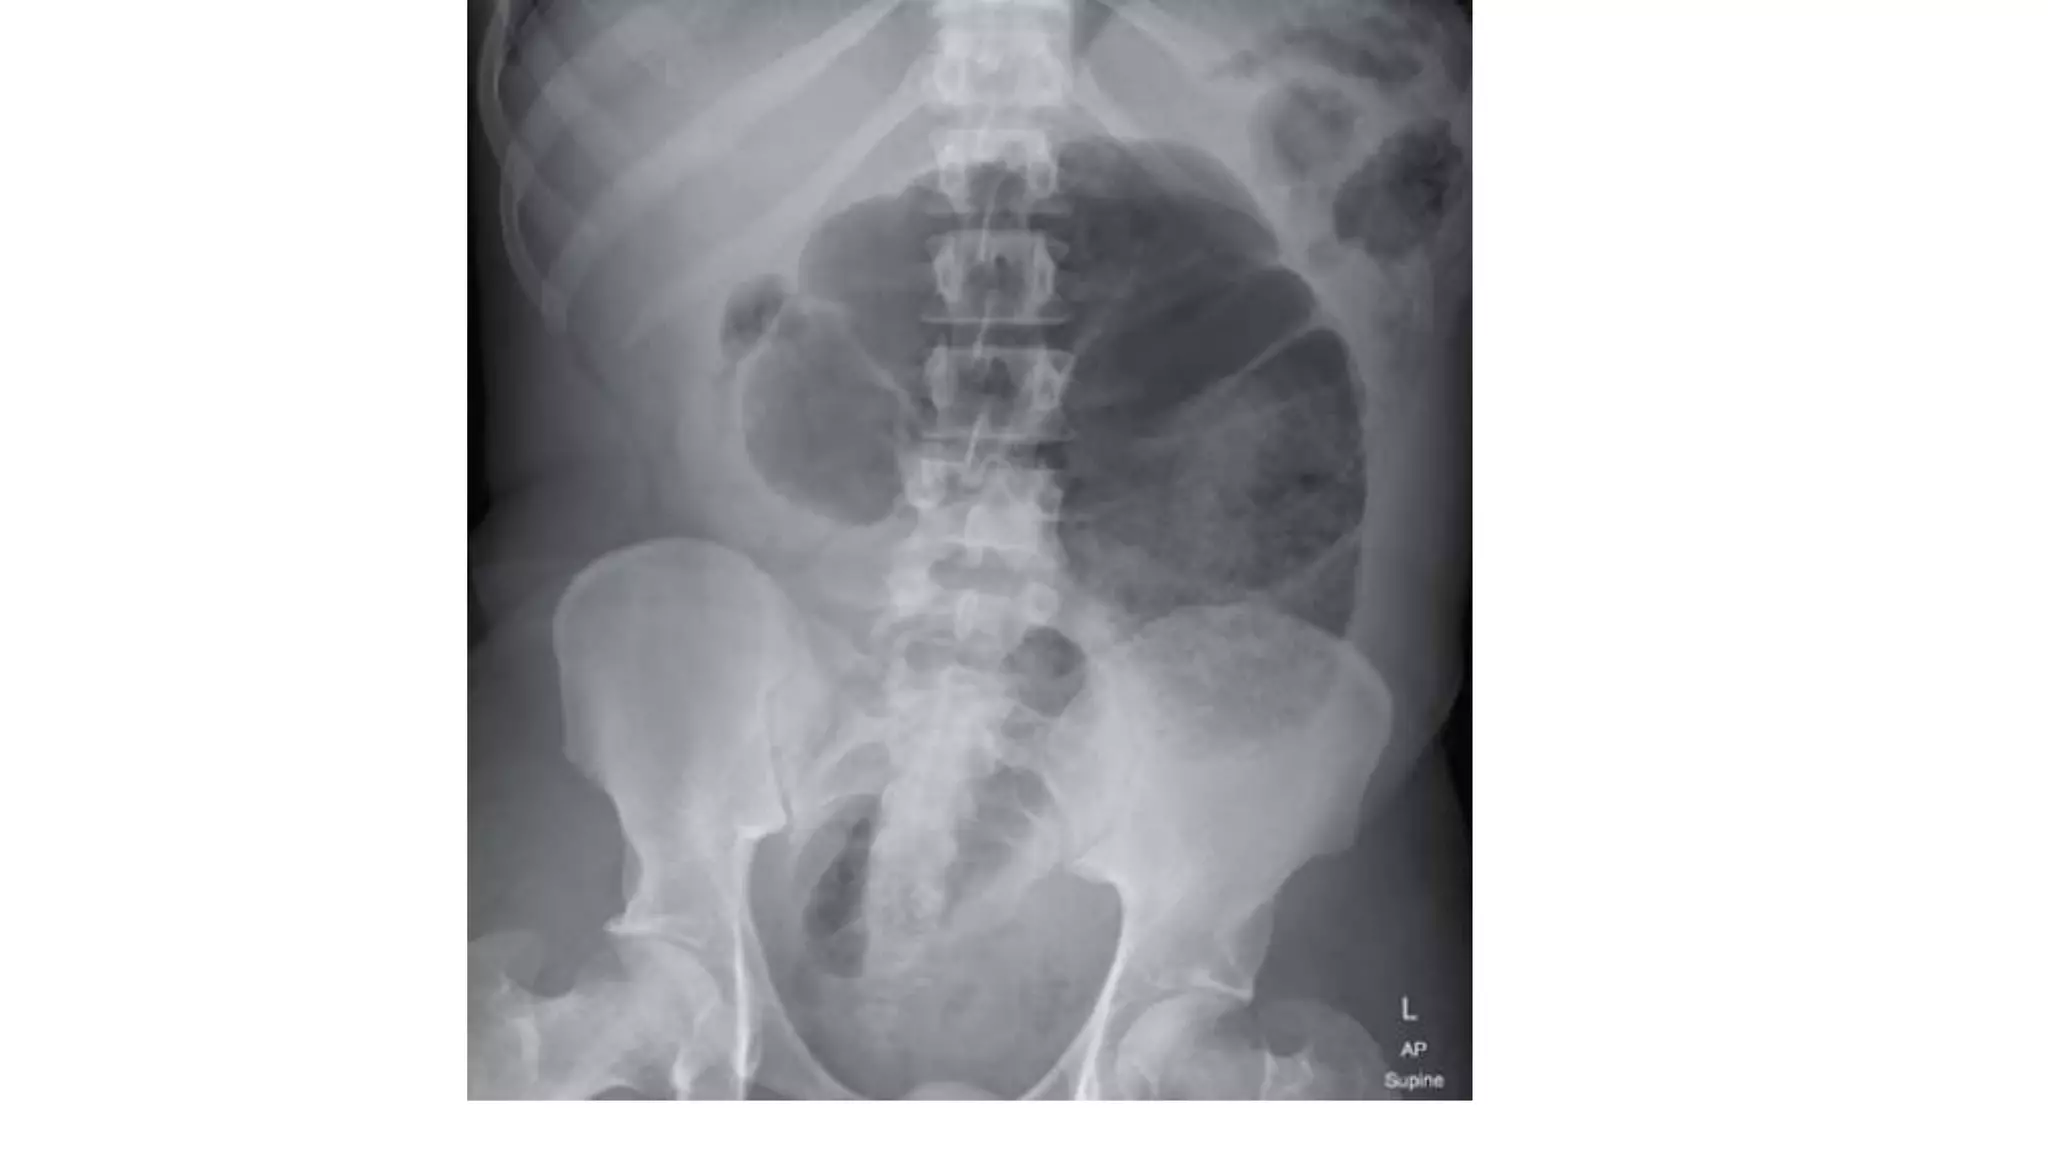

Radiological features in large bowel obstruction

• Colonic distension usually visualized in the periphery

• show the hustrations of the Taenia Coli.

• absence of rectal air and air fluid level if ileocecal valve incompetent

• May also demonstrate the cause of obstruction (volvulus)

• CT scan — In patients with axial torsion of the cecum (type I or II), a

computed tomography (CT) finding of the "whirl sign" (twisting of the

mesentery around the ileocolic vessels) is pathognomonic for cecal

volvulus. In addition, CT scan may also demonstrate signs of bowel

obstruction (a massively dilated cecum with associated small bowel

dilation) (image 5) or signs of colonic or small bowel ischemia (mural

thickening or mesenteric edema) [9]. In patients with a cecal bascule (type

III), CT scan shows the cecum folding upward, resulting in obstruction

without the axial twist of the mesentery (image 6).